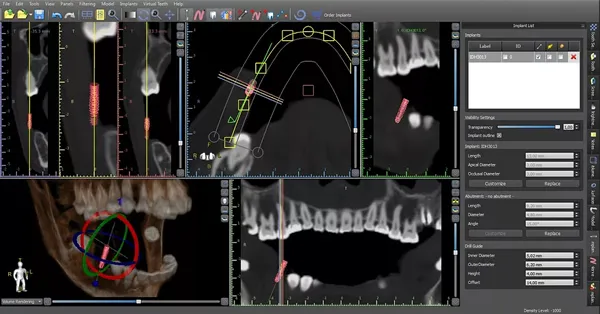

🔷シミュレーションソフト

CTで撮影した3Dデータを取り込み、手術の手順や埋め込みの角度、深さなどを綿密にシミュレーションすることで治療の精度を高めます。

従来の平面的なレントゲンでは確認できなかったあごの立体構造や神経の位置、炎症のある部位などを、三次元で詳細に映し出せる装置です。

診断精度が高まることで、これまで以上に安全性の高い治療が可能となりました。インプラントや根管治療、親知らずの抜歯など、多様な治療分野で活用されています。